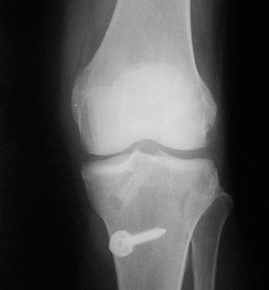

• ACL 손상 방사선 사진2